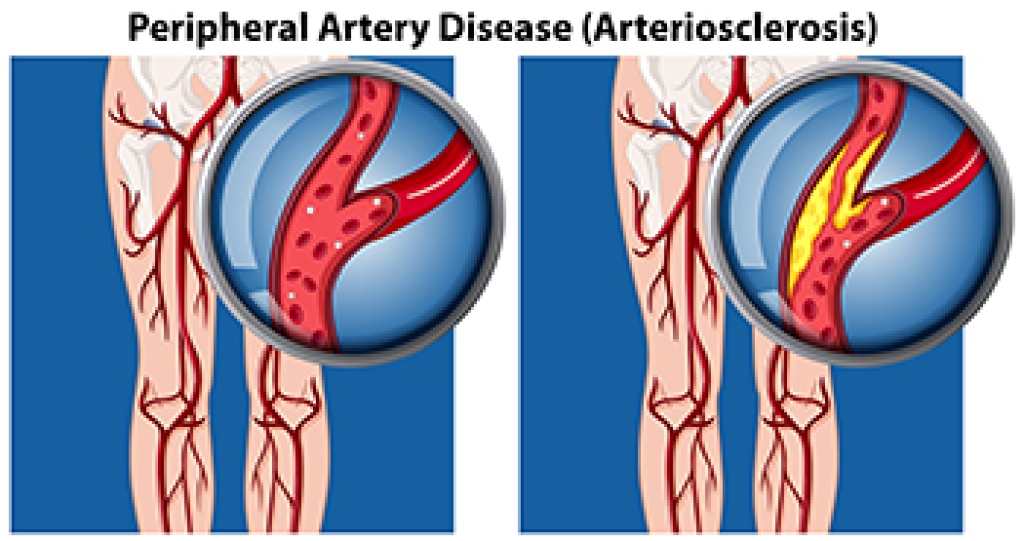

Wound care is the practice of taking proper care of a wound. This can range from the smallest to the largest of wounds. While everyone can benefit from proper wound care, it is much more important for diabetics. Diabetics often suffer from poor blood circulation which causes wounds to heal much slower than they would in a non-diabetic.

While it may not seem apparent with small ulcers on the foot, for diabetics, any size ulcer can become infected. Diabetics often also suffer from neuropathy, or nerve loss. This means they might not even feel when they have an ulcer on their foot. If the wound becomes severely infected, amputation may be necessary. Therefore, it is of the upmost importance to properly care for any and all foot wounds.